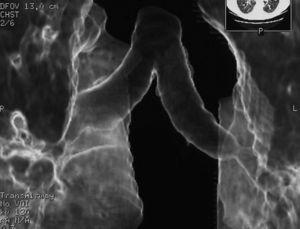

Pulmonary vein obstruction is usually an early complication, occurring during the first few hours after transplantation, and causes severe symptoms. Marked hypoxia, pulmonary edema, and pulmonary infiltrates are observed. If the lower lobe is more severely affected, a high suspicion for such a complication is warranted, and an early additional diagnostic test should be ordered. The initial test should be a transthoracic or transesophageal echocardiogram, in spite of this test being only useful for diagnosis when performed by an experienced operator, due to a challenging visualization and interpretation after recent surgery 6. Alternatively, chest CT angiography can be used, which also allows artery suture and distal vascularization to be assessed and reconstructions to be produced. CT angiography establishes the diagnosis in most cases. Anticoagulation using heparin and clinical course monitoring is used to manage partial thromboses and stenoses. In the event of a complete vein obstruction or a poor course, in patients with a very recent surgery, re-transplantation or lobectomy for double-lung transplantations, may be needed. If the patient is in a stable condition, several days have elapsed, and anatomic characteristics are favorable, an angioplasty with dilation and stent implant can be considered.

Arterial suture complications are usually less common and are found later. They result in persistent hypoxia and pulmonary hypertension. Diagnosis is based on CT angiography and/or arteriography. Some degree of arterial suture stenosis with no clinical significance is commonly found in CT angiography, due to donor-receptor size discordance or to the suture itself. Significant stenoses are due to kinking or thrombosis at the suture level. The former are usually treated win angioplasty and dilation, whereas usual therapy for the latter is stent implant if required. Anticoagulation is used for thrombotic cases 7.

Figure 3. Coronal view in CT angiography showing complete lower pulmonary vein obstruction after left lung transplantation.